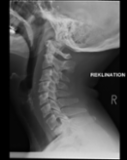

Acute calcific deposit on the enthesis of the longus colli muscle

The severe cervical spine pain prompted an emergency MRI examination, which showed a clear prevertebral inflammatory soft tissue process. On close inspection, a calcific deposit anterior to the dens axis can already be suspected on MRI (especially T2 or axial T1fs Gd+). The calcium depot is only shown very fluffy on X-ray and CT, suggesting an acute stage with precipitation/resorption of the calcific milk.